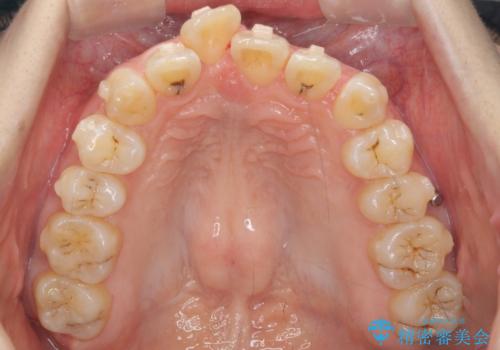

- 前歯の突出を主訴に来院。

上の奥歯を後ろに下げて治療をしました。

矯正用のミニスクリューを使用しています。

上の前歯もIPR(エナメル質をわずかに削る処置)を行っています。